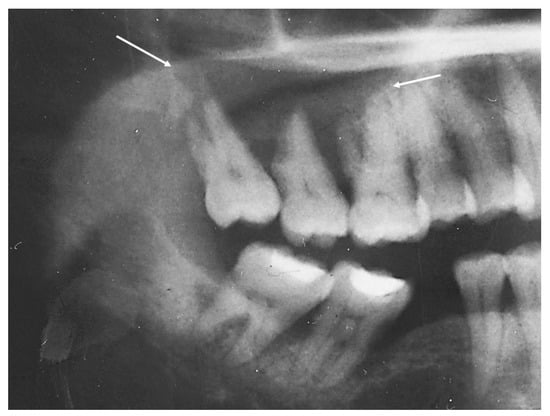

2.2. Case 2

| Location | Right maxilla | Right mandible | Right maxilla |

| Morphology | Infiltrative, non-encapsulated malignant neoplastic odontogenic epithelial proliferation with clear cell component in a dense fibrous connective tissue stroma. Neoplastic cells arranged in anastomosing trabeculae. Nuclear hyperchromasia and pleomorphism surrounded by clear, vacuolated cytoplasm. Stroma was hyalinized, densely collagenized, hypocellular, and hypovascular. | Neoplastic odontogenic epithelial proliferation diffusely infiltrated the connective tissue stroma. Neoplastic cells arranged in islands of variable size, trabeculae, and nests. Nuclei were hyperchromatic, central, and pleomorphic surrounded by clear cytoplasm. | Infiltrative odontogenic epithelial neoplasm intermixed with eosinophilic dentinoid matrix. Neoplastic cells arranged in infiltrative, non-encapsulated sheets, cords, and nests of polygonal cells with central hyperchromatic and slightly pleomorphic nuclei surrounded by clear cytoplasm and occasional pale eosinophilic cytoplasm. Occasional mitotic figures were noted. Neoplastic epithelial sheets and cords blended with eosinophilic cellular matrix without cellular rimming consistent with dentinoid deposits. |

| Procedure | Right maxillectomy with negative margins | Left mandibulectomy Right temporomandibular joint arthroplasty Left fibula free flap | Right maxillectomy without orbital exenteration Right selective neck dissection Forearm free flap Four months adjuvant radiation |